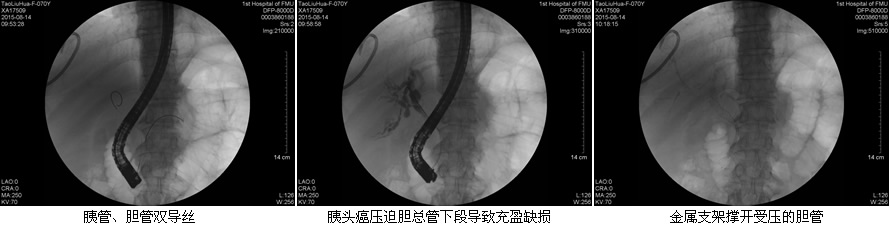

目前ERCP适应症主要包括:原因不明的阻塞性黄疸疑有肝外胆道梗阻者;疑有各种胆道疾病如结石、肿瘤、硬化性胆管炎等诊断不明者;疑有先天性胆道异常或胆囊术后症状再发者;胰腺疾病:胰腺肿瘤、慢性胰腺炎、胰腺囊肿等。在这50余例病例中,包含了内镜下乳头活检术、乳头括约肌切开取石术、胆管内支架引流术、鼻胆管引流术、“三镜”联合治疗胆总管结石等,患者术后无明显并发症发生,获得了良好的疗效,使我院ERCP诊疗技术进入一个崭新的时代。

在工作中,该团队始终坚持“用科研的态度对待每一例患者!”无论是小小的十二指肠乳头活检术,还是难度较大的胃毕Ⅱ术后乳头切开取石术,乃至肝门部高位胆管癌内支架置入术,“安全至上”的理念始终体现在每一位患者身上。无论简单还是复杂,ERCP团队的每一位成员,术前都严格评估适应症和禁忌症,术中规范操作,术后应按预案防治并发症,确保了每一例患者的安全。